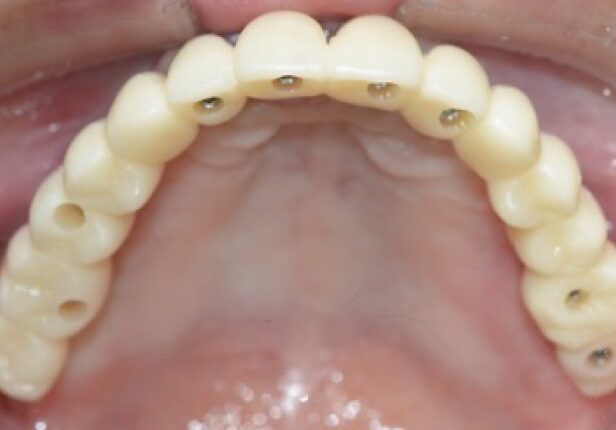

Maxila - Caso completo

caso de estudo

Panorâmica pré-cirúrgica

Antes da cirurgia

Colocação do implante

Panorâmica pós-cirurgia

Coroa provisória

Antes da colocação da coroa final

Coroa Final

Panorâmica Final da Coroa